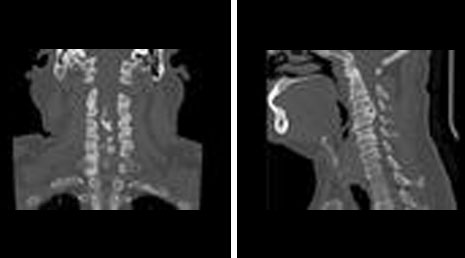

1. Atlanto-axial dislocation

2. Arnold chiari malformation with syrinx.

3. Anterior communicating artery aneurysm- coiling.